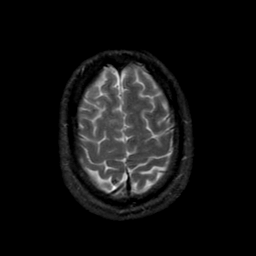

MR Study #21, November 3, 1991 -- Slice #42